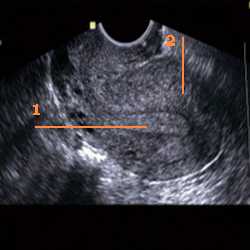

Медицинская диагностика: Гиперплазия эндометрия на УЗИ